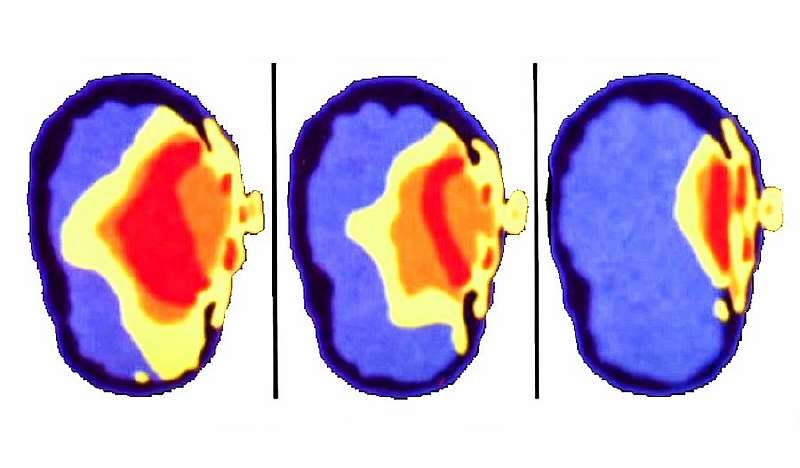

У неионизирующего излучения — а именно такое испускают наши смартфоны — энергии для подобного воздействия на клетки недостаточно. Конечно, части тела, расположенные в непосредственной близости от антенны, в любом случае поглощают некоторое количество волн. Для измерения этого количества даже есть отдельный показатель. Он называется SAR (Specific Absorption Rate), и его значения в разных странах строго регламентированы. К примеру, в Европе нельзя продавать смартфоны, SAR которых превышает 2 Вт/кг, в США эти требования еще более строгие — 1,6 Вт/кг.